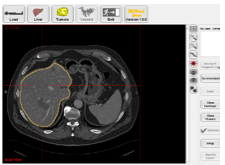

Lebersegmentierung (halbautomatisch)

Nach dem Laden eines DICOM-CT Datensatzes über CD, Netzwerk oder PACS kann die Leber mit wenigen Mausklicks segmentiert werden. Während die Schnittbilder die gesamte Anatomie zeigen, beschränkt sich die 3D-Ansicht auf den Bereich der Leber.